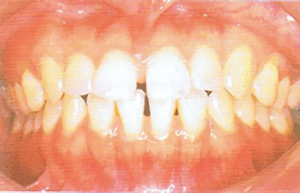

type01

• 歯の列がでこぼこしていると感じる

• 歯に食べカスが残りやすい

• 笑うと犬歯(八重歯)が見える

「叢生(そうせい)/乱杭歯、八重歯」である可能性があります。顎の大きさと歯の大きさのバランスが悪いために、歯がでこぼこに生えたり、重なっている状態です。歯が磨きにくく、そのため虫歯や歯肉炎を起こしやすくなります。歯周病にまで発展すると、若くても歯を失う可能性があります。